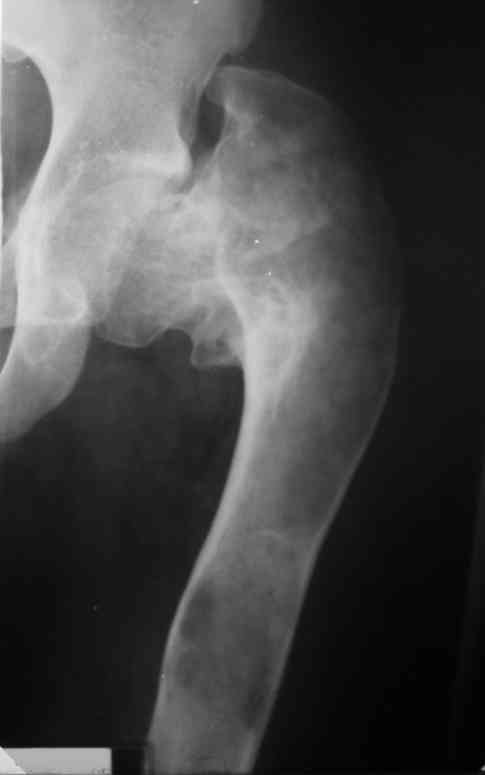

ВН>> Подросток 14 лет получил патологический перелом шейки левого бедра

ВН>> месяцев выполнить коррекцию ШДУ, что частично устранит

Интересует возможность одномоментного устранения очага ФД и корригирующей остеотомии, хотя я склоняюсь к двухэтапной тактике.Когда я впервые увидел этого подростка, сразу после снятия гипсовой повязки, консолидации не было и в планах была экскохлеация с медиализирующей вальгирующей остеотомией. Сейчас, когда консолидация отчетливая, возможно ограничимся только вальгизацией.На мой взляд надо оствить приемлемые условия для последующего ТЭП. Удивляет столь закрепившееся в практике мнение о возможности спонтанного восстановления костной после патологических переломов при кистах и ФД.

Около 16 лет наблюдаю пациента с ФИБРОЗНОЙ ДИСПЛАЗИЕЙ левой нижней конечности, полиосальная форма. Прилагаю рентгенснимки.